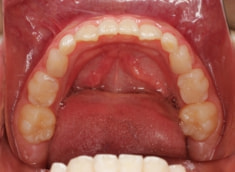

治療開始から約1年1ヶ月後

フェイスマスクによる上顎の前方牽引の効果が認めらます。

治療前後の重ね合わせから、フェイスマスクの効果が認められます。